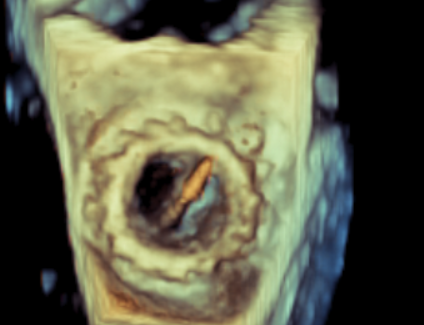

术中影像监护与评估(DSA&TEE)

原生物瓣少量反流

过瓣流增快,呈“五彩状”